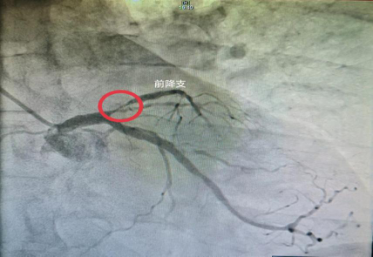

冠状动脉造影是应用影像学的方法,将冠状动脉正常或异常的形态学直观地显示出来,提供冠状动脉病变的部位、性质、范围、侧支循环状况等准确的资料,它是诊断冠心病的一种常用而且有效的方法,是一种较为安全可靠的有创诊断技术,现已广泛应用于临床,被认为是诊断冠心病的“金标准”。

局麻后,常规选择腕部的桡动脉进行穿刺(特殊情况也可选择股动脉),从而将导管送至心脏表面的冠状动脉,并注入造影剂。医生可根据冠状动脉造影情况明确冠状动脉的形态,进而有效评价冠状动脉病变的严重程度和范围,为治疗方案的制定提供可靠依据。